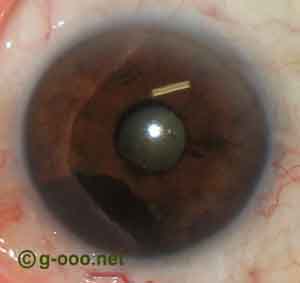

Melanoma da porção inferior da íris, de uma mulher de 83 anos de idade. |

Melanoma da porção inferior da íris, de uma mulher de 83 anos de idade. |